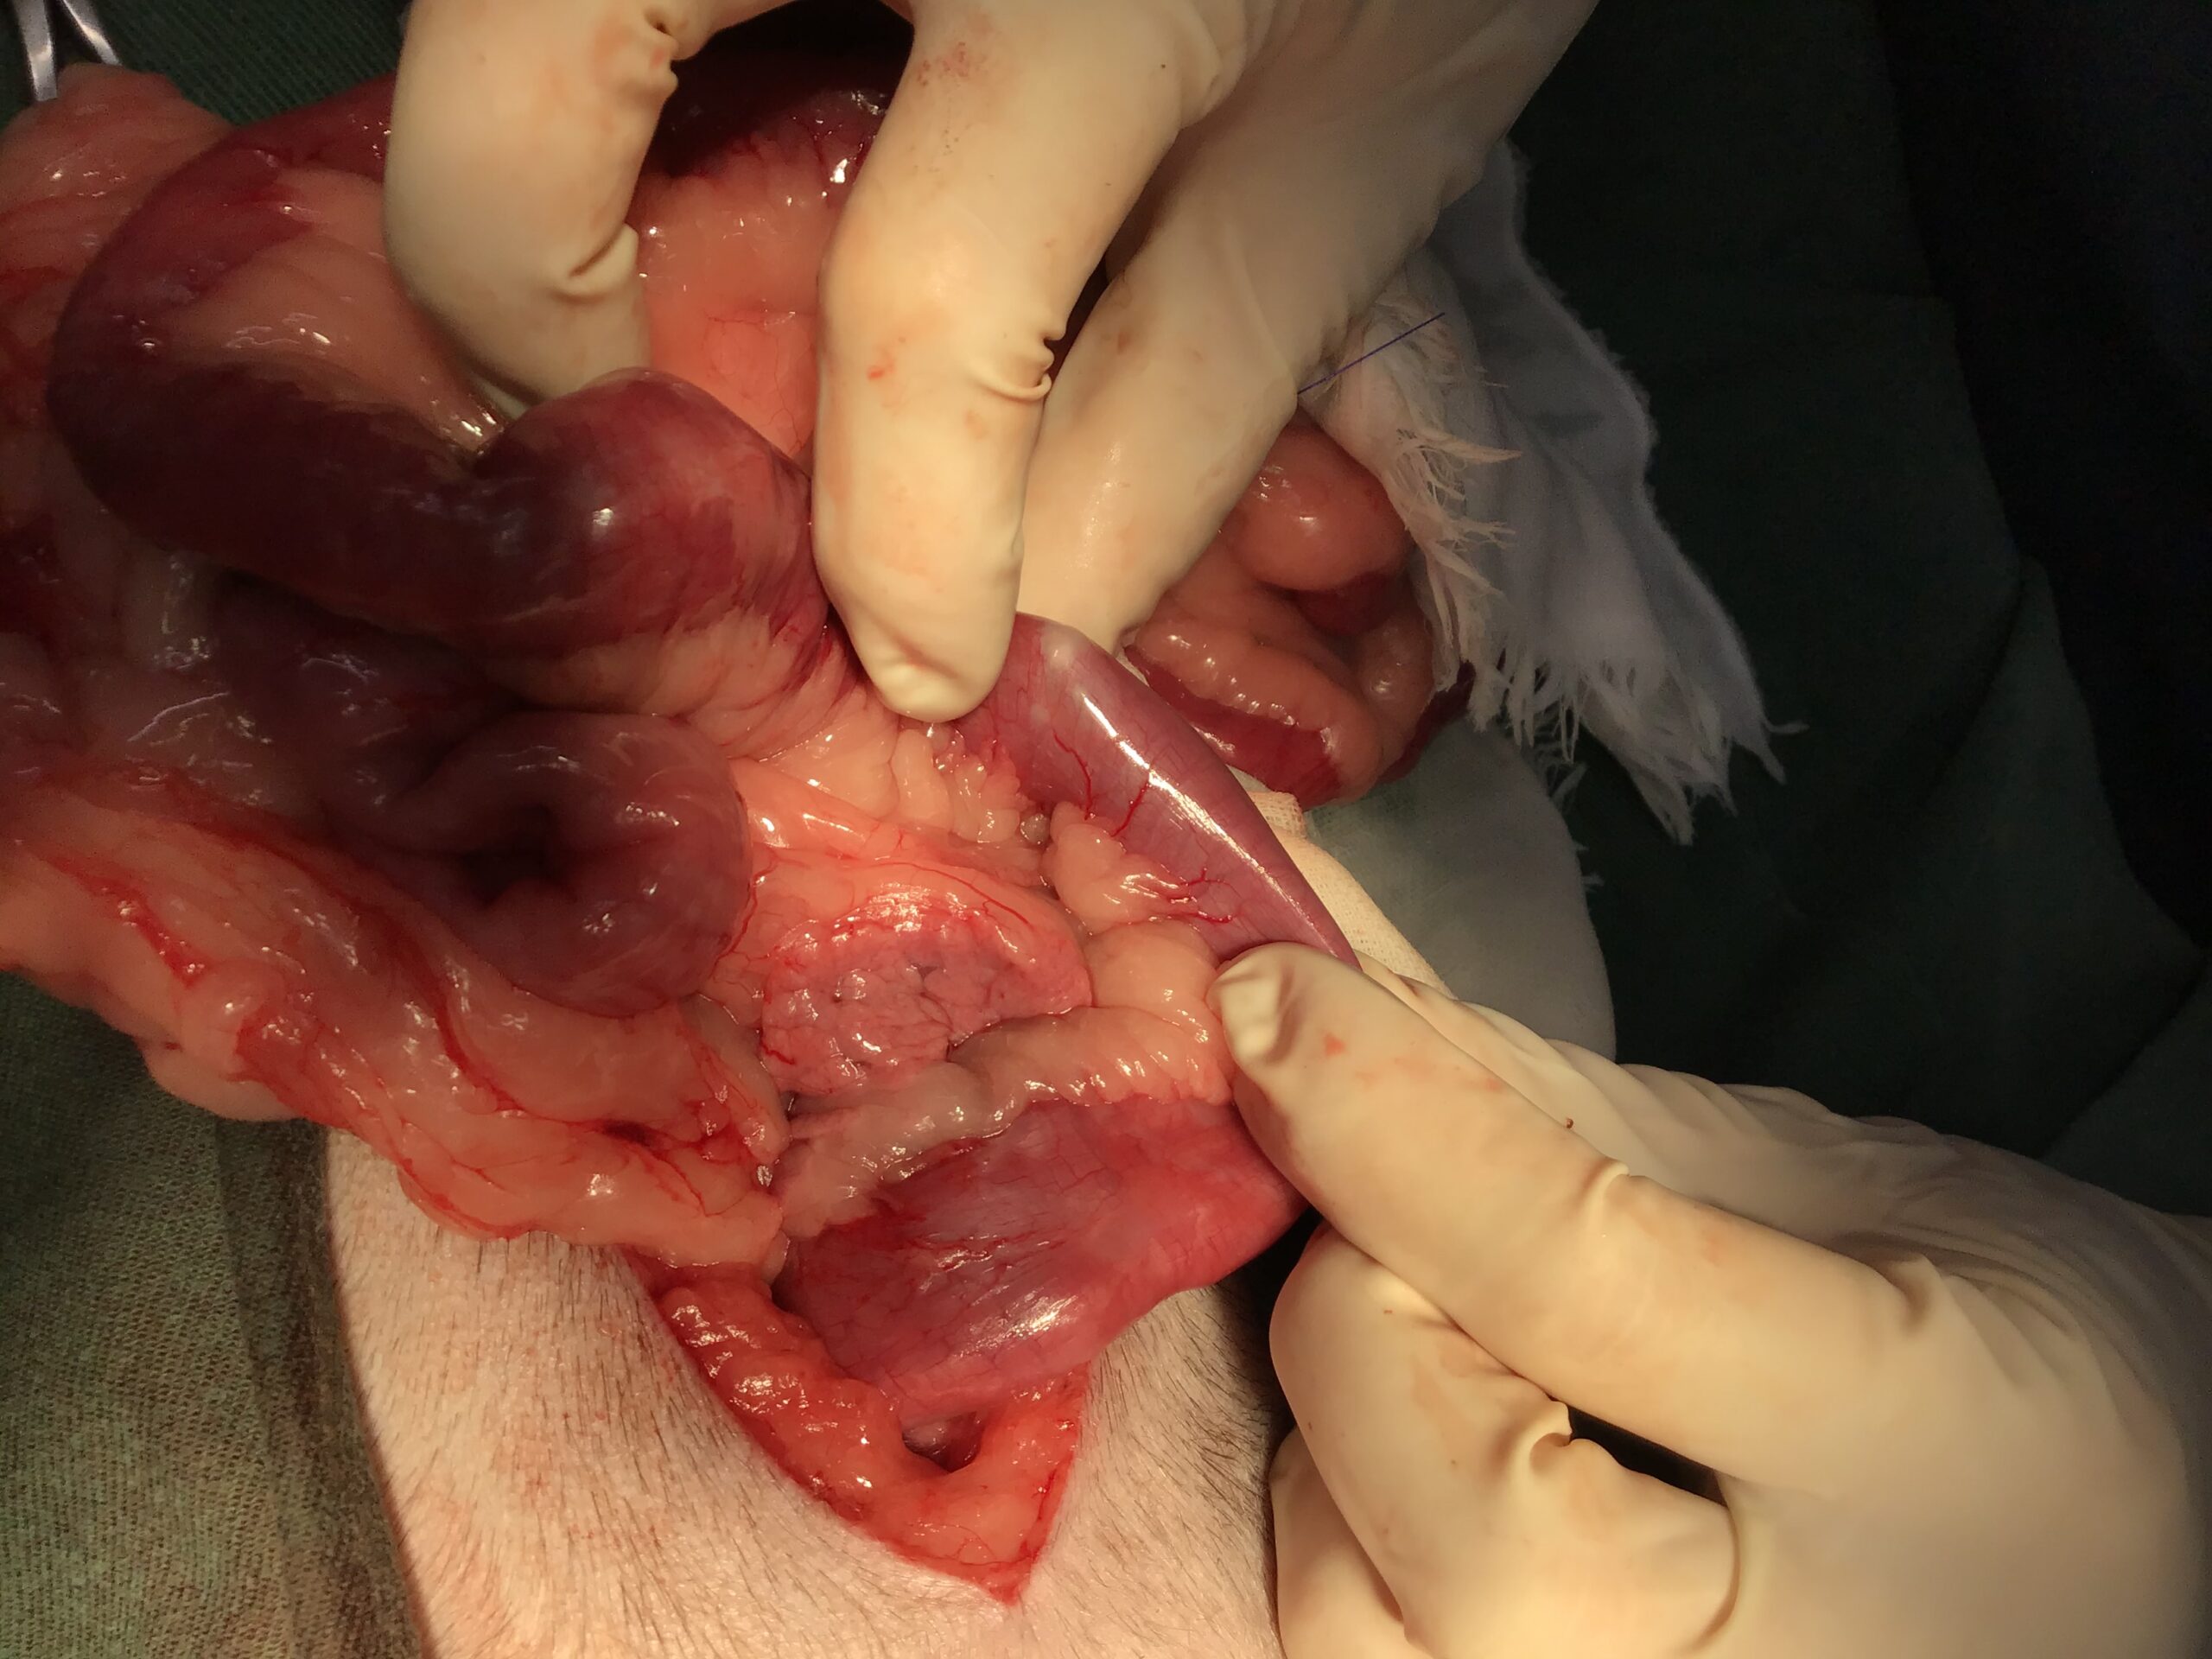

最悪の事態を防ぐため、緊急で胃および十二指腸の切開手術を実施して異物を摘出しました。術前・術中には、膵炎の治療薬や制吐剤、抗生剤を点滴で持続的に投与し、全身状態を安定させながら慎重に手術を進めました。

消化管を切開する手術は、術後のケアが極めて重要です。本症例では、術後にいくつか乗り越えるべき課題がありました。